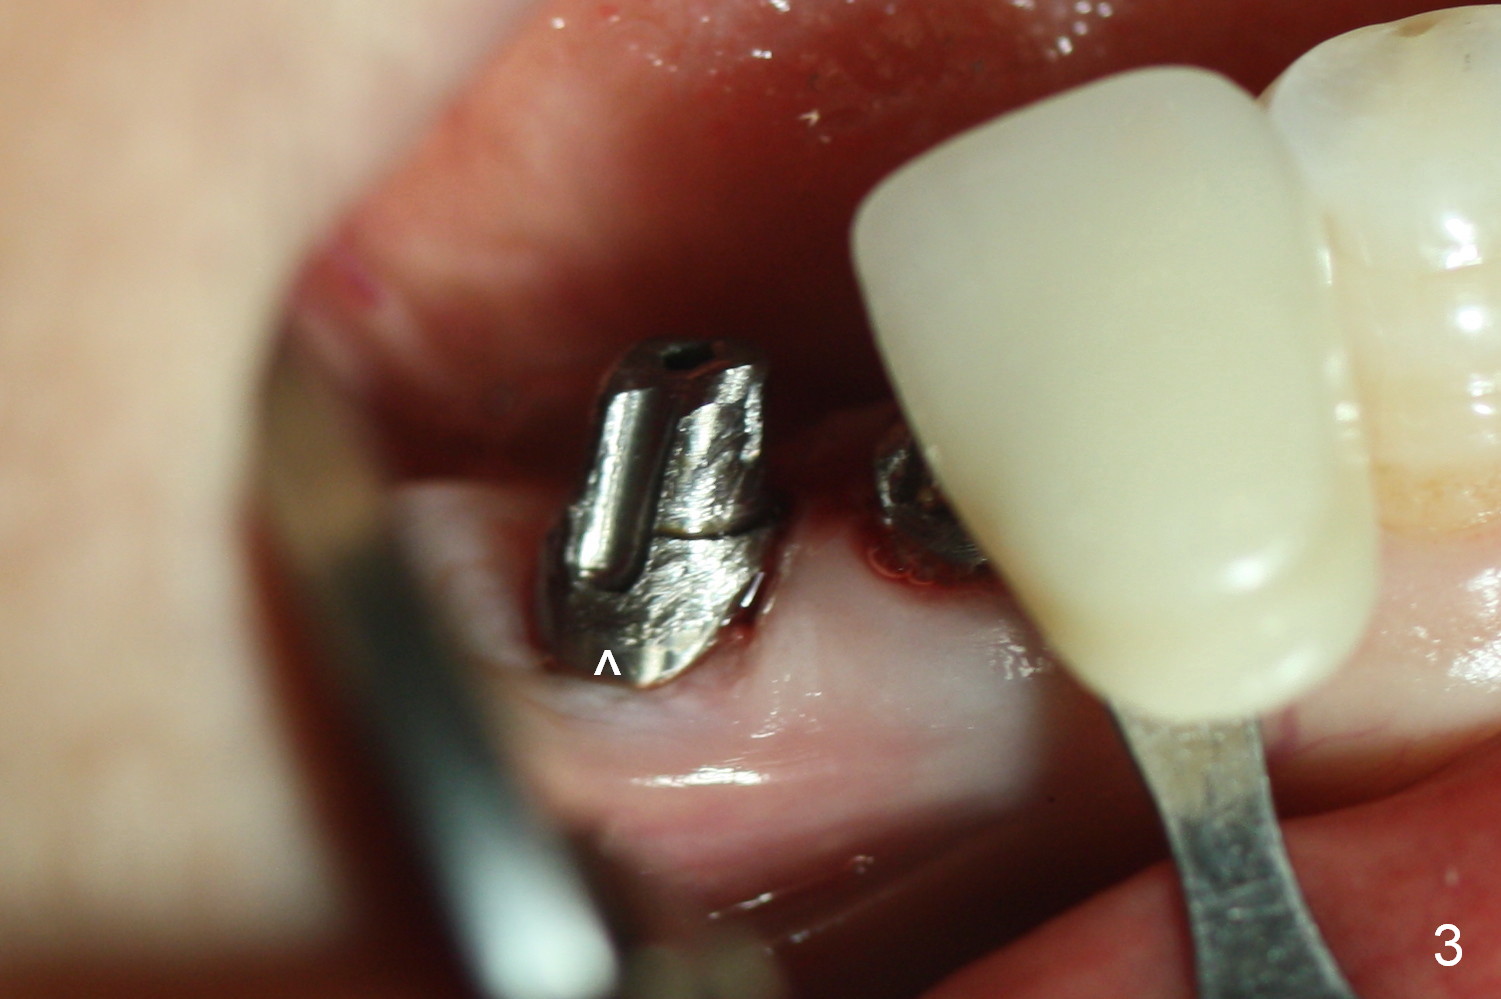

A 55-year-old lady (WJ) complains of palpation pain in the buccal vestibule over #29 implant, 5 months postop (immediately before cementation, Fig.4 *). Is the implant placed too buccally or there is buccal plate resorption after placement?

Four months and a half, the buccal margin has to be extended (Fig.3 ^). A month later, gingival recession becomes more obvious (Fig.4 ^ with exposure of the rough surface of the implant). Occlusal view demonstrates the buccal position of the implant and abutment at #29 (Fig.5). CBCT will be taken to confirm the malpositioning. If it is confirmed, the abutment and implant will be removed and un-torqued. The lingual bone will be removed; osteotomy will be also extended apically cautiously. The same or longer implant will be placed immediately. Probably two 1 piece implants will be placed at the same time at the site of #30, since the ridge is narrow.